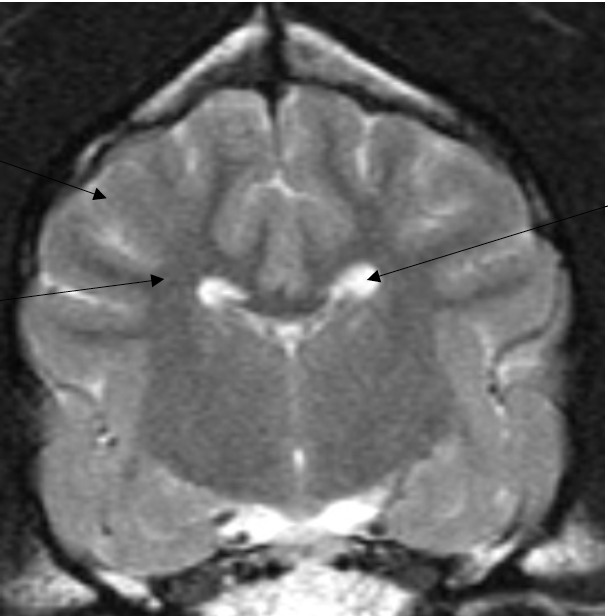

what structures are shown

corpus callosum (left)

internal capsule (right)

1. corpus callosum: a mass of fibres that connect right and left cerebral hemispheres

2. internal capsule: fibres running to and from the brainstem